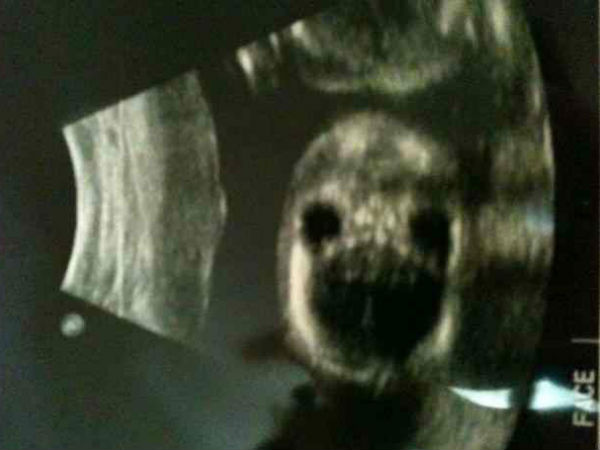

ಚಿತ್ರ#4 ಚಿತ್ರಕ್ಕೆ ಭಂಗಿ ನೀಡುತ್ತಿದೆಯೇ?

ಚಿತ್ರ ತೆಗೆಯುವವರು ಬಂದಾಗ ಎಲ್ಲರೂ ಇದಕ್ಕೆ ಸೂಕ್ತ ಭಂಗಿ ನೀಡಲು ಕೊಂಚ ಮುಗುಳ್ನಗುತ್ತಾರಲ್ಲಾ, ಈ ಕಲೆಯನ್ನು ಈ ಮಗು ಗರ್ಭದಲ್ಲಿಯೇ ಕಲಿತು ಕೊಂಡಂತಿದೆ. ಈ ಚಿತ್ರದಲ್ಲಿ ಬಾಯಿಯನ್ನು ಪೂರ್ಣವಾಗಿ ತೆರೆದು ಚಿತ್ರಕ್ಕೆ ಭಂಗಿ ನೀಡುವಂತೆ ಕಾಣುತ್ತಿದೆ. ಈ ಮಗುವಿನ ಚಿತ್ರ ತೆಗೆದಾದ ಬಳಿಕ ಬಾಯಿ ಮುಚ್ಚಿದ್ದರಿಂದ ಇನ್ನೊಂದು ಚಿತ್ರದಲ್ಲಿ ಹಾಗೇ ಮೂಡಿಬಂದಿದೆ.